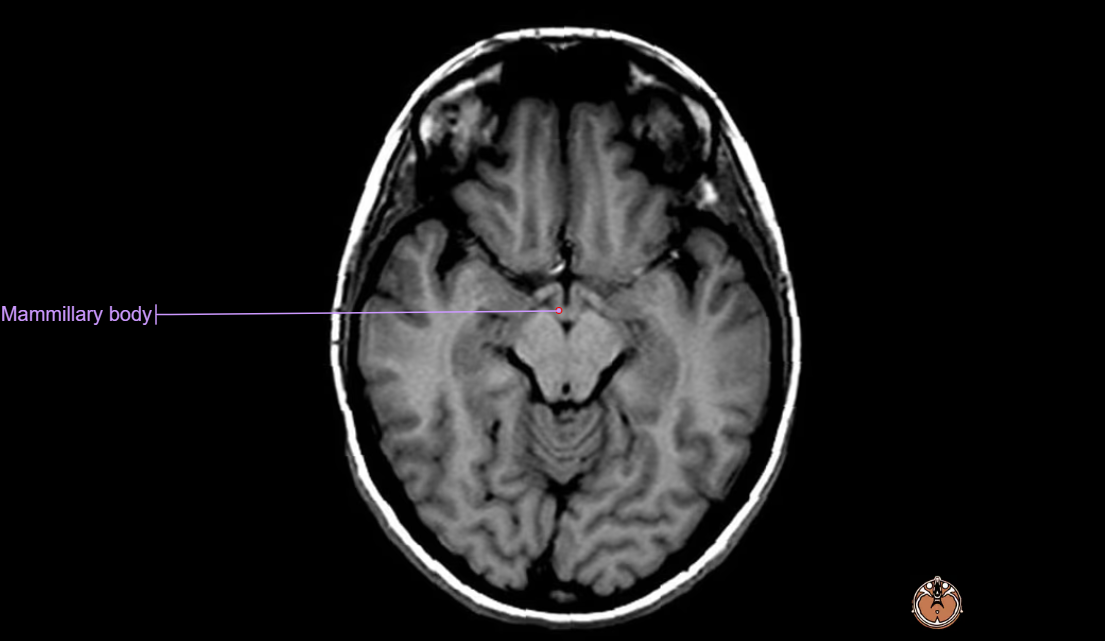

- 뇌 MRI(brain MRI) 영상은 T2 flair 및 brain DWI 영상에서 아래와 같은 영역에서 양측성 signal intensity의 증가 소견을 보이게 된다.

- mammillary body

- 급성 베르니케 뇌병증의 병변은 vascular congestion(혈관 충혈), microglial proliferation(뇌 대식세포의 증식), petechial hemorrhage(점상 출혈)에 의해서 발생하며, 만성적으로는 demyelination(탈수초화), gliosis, neuropil의 소실로 이어지게 된다. 신경의 소실은 상대적으로 medial thalamus에서 현저히 발견되고, mamillary body의 위축은 베르니케 뇌병증, 코르사코프 증후군의 환자 최대 80%에서 확인되고 있다.

- 흔히 병변이 확인되는 구조물 : the 3rd ventricle, aqueduct, fourth ventricle, dorsomedial thalamus, locus ceruleus, peri-aqueductal gray, ocular motor nuclei, vestibular nuclei, fornices, septal region, hippocampus, cerebral cortex 등에서 보이며, 주로는 대칭적으로 확인된다.